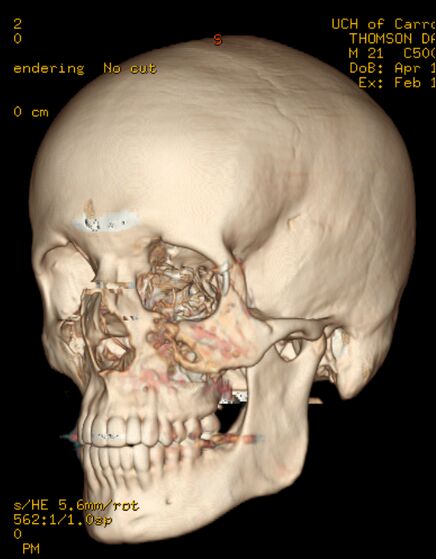

| Danny Thomson estava jogando beisebol com o irmão menor quando de repente este acertou a bola em cheio que veio, a mais de 160 por hora, em direção ao seu rosto. A bolinha acertou sua bochecha esquerda e fez um tamanho de um estrago que precisou de cirurgia para ser reparado. Vejas as imagens: |

dois olhos roxos eu não sei, mas a 4° foto eh o rabisco q os medicos fazem antes da cirurgia, pra sabe aonde eh q tem q mexe e tals...

a bola rachou o cranio dele, ou eu que vi a tomografia zuada?????

Tomografia 3D show de bola !!!!